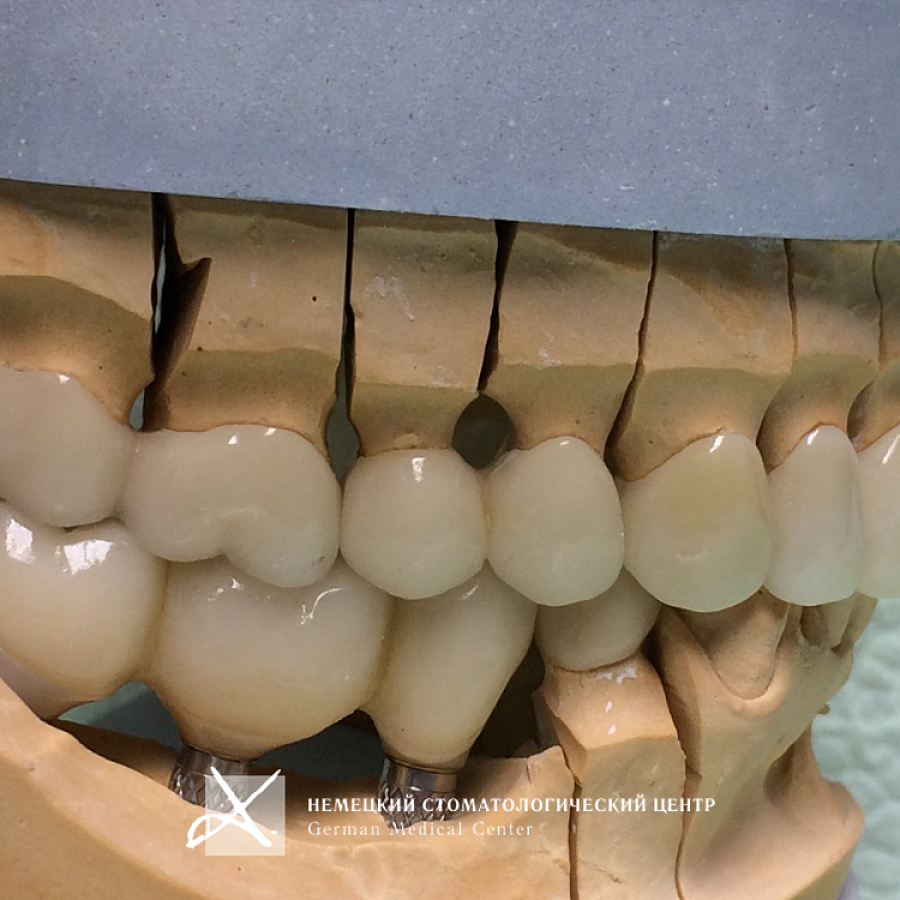

Пациентке проведено полноценное восстановление зубных рядов конструкциями с опорой на зубы и имплантаты. Коронки и абатменты изготовлены из диоксида циркония. Во время подготовительных мероприятий пациентка пользовалась временными конструкциями.